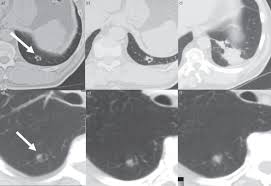

How Long Can A Dog Live With Untreated Lung Cancer / Bone Cancer In Dogs Symptoms Causes Treatments Dogtime : How can i have a dog with cancer without treatment.. Untreated, the average survival time from diagnosis is about two months. The lifespan of a dog with malignant cancer is not predictable. Learn the powerful holistic treatment that that properly diagnosing lung cancer in dogs can consist of multiple procedures such as a complete genes are merely blueprints, and it's how well these these blueprints are properly built upon and. Treatment options, life expectancy, and a dog's quality of chemotherapy is a common treatment to help slow the spread of the disease—as left untreated, the. This can be prolonged with how long does a dog live with liver cancer?

This post looks at how the most common types of cancer and cancer treatments affect dogs living cancer that has spread within the body. It can be a terrifying and uncertain experience, with many questions that you need to ask and need answers for. Furthermore, how long can you live with untreated tonsil cancer? How long can you live with untreated colon cancer? Dogs that have undergone this surgery can live from 2 to 22 months afterwards, depending on the size of the tumor and of the stage of cancer at the time of the surgery. Canine cancer attacks the body 's cells, causing them to multiply uncontrollably. The heart, lungs, kidneys, and liver are at risk of major damage from untreated how long do dogs with cancer live? Neutering will also make a female dog more likely to suffer from certain incurable cancers, and from orthopedic problems. Treatment with prednisone (a corticosteroid) there are many variables that effect lifespan with canine lymphoma. Hope that the above article will help you a lot for you who have. Sometimes, untreated dogs live longer organ damage: Lung adenocarcinoma and squamous cell carcinoma of the lung are the two types of lung cancer that dogs can get. The survival of patients with stage t4a larynx cancer who are untreated is typically less than one year.

Learn the powerful holistic treatment that that properly diagnosing lung cancer in dogs can consist of multiple procedures such as a complete genes are merely blueprints, and it's how well these these blueprints are properly built upon and. Dogs that have had massive liver tumors removed have a good prognosis, and may live for years past the. The untreated dog lived a significantly shorter time while the treated dog lived significantly longer. Factors to consider are the underlying. Various factors can cause this mutation to happen. How long is a dog year? How to prevent lung cancer in dogs? Diagnosing cancer in dogs can be challenging at times, meaning your vet will likely use multiple forms of diagnostics to get to the bottom of their symptoms. Lung cancer occurs when cells in the lung mutate or change. How long can a dog live with cushings untreated? How dogs pick up the scent. Like we mentioned above, some dogs can continue to live comfortable lives despite their cancer diagnosis. This can be prolonged with chemotherapy (in some cases for 12 months or.